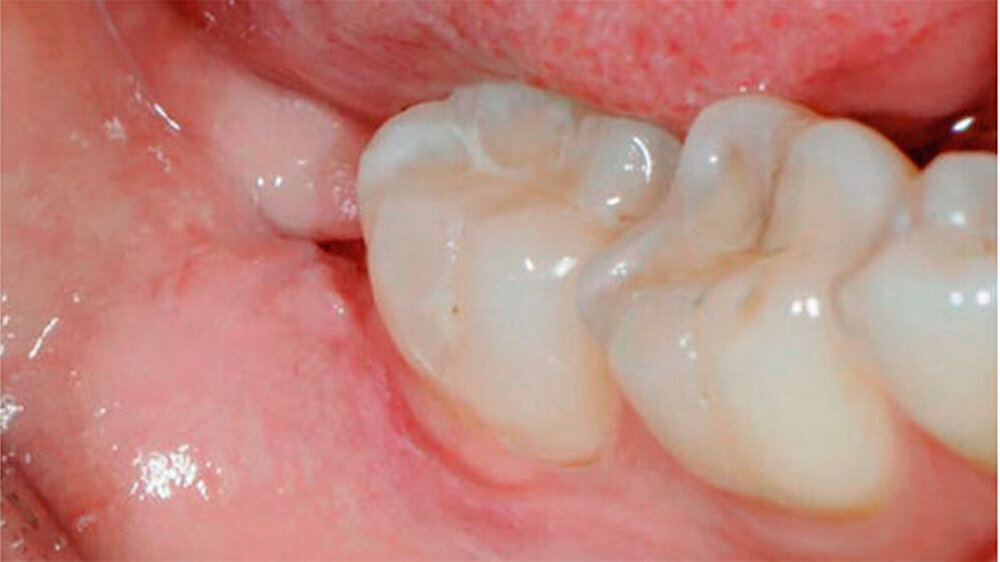

Nach einem Jahr wurde eine radiologische sowie eine klinische Nachkontrolle durchgeführt. Die Patientin war beschwerdefrei. Radiologisch war eine deutliche Migration des Wurzelblocks in kranialer Richtung sichtbar, die Wurzelspitze war radiologisch nicht über den Mandibularkanal projiziert. Die Schleimhaut war nicht durchbrochen (Abb. 1l und 1m). In diesem Fall sollte eine vollständige Entfernung des Wurzelrests angestrebt werden.